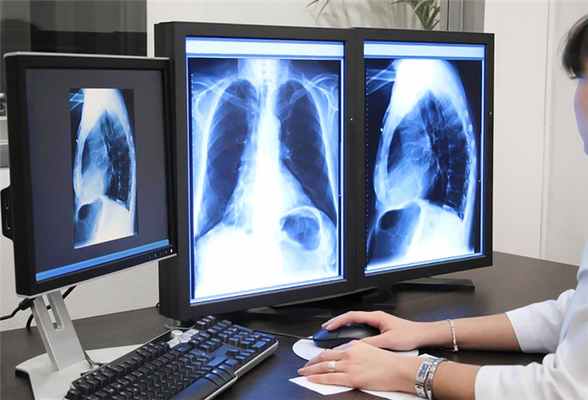

Современные методы рентгенологических исследований классифицируются, прежде всего, по типу аппаратной визуализации рентгеновских проекционных изображений. То есть основные виды рентгенодиагностики дифференцируются тем, что каждый построен на использовании одного из нескольких существующих типов приемников рентгеновского излучения: рентгеновская пленка, флюоресцирующий экран, электронно-оптический рентгеновский преобразователь, цифровой детектор и др.

Рентгенологические методы исследования, за короткий исторический период своего развития и использования в медицине, превратились в один из ведущих способов научного и клинического исследования. Посредством использования рентгенографии, рентгеноскопии, флюорографии, компьютерной томографии, врач получает возможность без инвазивного вмешательства наблюдать за функционированием многих органов и систем организма в норме и при патологии. Эта особенность делает рентгенологические методы одними из важнейших в диагностике заболеваний. С помощью рентгенодиагностики обеспечивается своевременное распознавание различных заболеваний, в том числе и самых частых и грозных – травматические повреждения, воспаления, новообразования. Предметом изучения рентгенологии, как науки, служит весь организм в целом, и поэтому можно считать эту науку и методы применяемые ею - универсальными.

При всех видах рентгенологических исследований, пучок рентгеновских лучей направляется на исследуемую часть тела. Излучение, прошедшее через тело пациента, попадает на пленку или цифровой приемник, который передает полученное изображение на экран компьютера. Изображение на пленке становится видимым после фотообработки.

Рентгенологическое исследование основано на особом свойстве рентгеновских лучей проникать через плотные непрозрачные среды и поглощаться ими в неодинаковой степени в зависимости от их химического состава и физических свойств. В результате на светочувствительном экране, воспринимающем рентгеновские лучи, прошедшие через участок человеческого тела, получают плоское изображение внутренних органов. Различные органы и ткани дают на экране тени неодинаковой интенсивности, что и создает возможность отличить их друг от друга. Например, на фоне прозрачных для рентгеновских лучей легких можно исследовать сердце (установить размеры, положение), определять воспалительные участки в легких. Особенно успешно прямое рентгенологическое исследование применяется при диагностике целостности костей скелета, поскольку костная ткань в наибольшей степени поглощает рентгеновские лучи и очень хорошо контрастируется на фоне остальных тканей человеческого тела.

Рентгеновские исследования проводятся при помощи специализированного рентгенологического оборудования, работающего на основе электромагнитного излучения.

Современная рентгенодиагностика подразумевает линейную и спиральную томографию, флюорографию, рентгенографию, рентгеноскопию, мультиспиральную компьютерную томографию, радионуклидную сцинтиграфию, интервенционную радиологию и другие методы исследований.